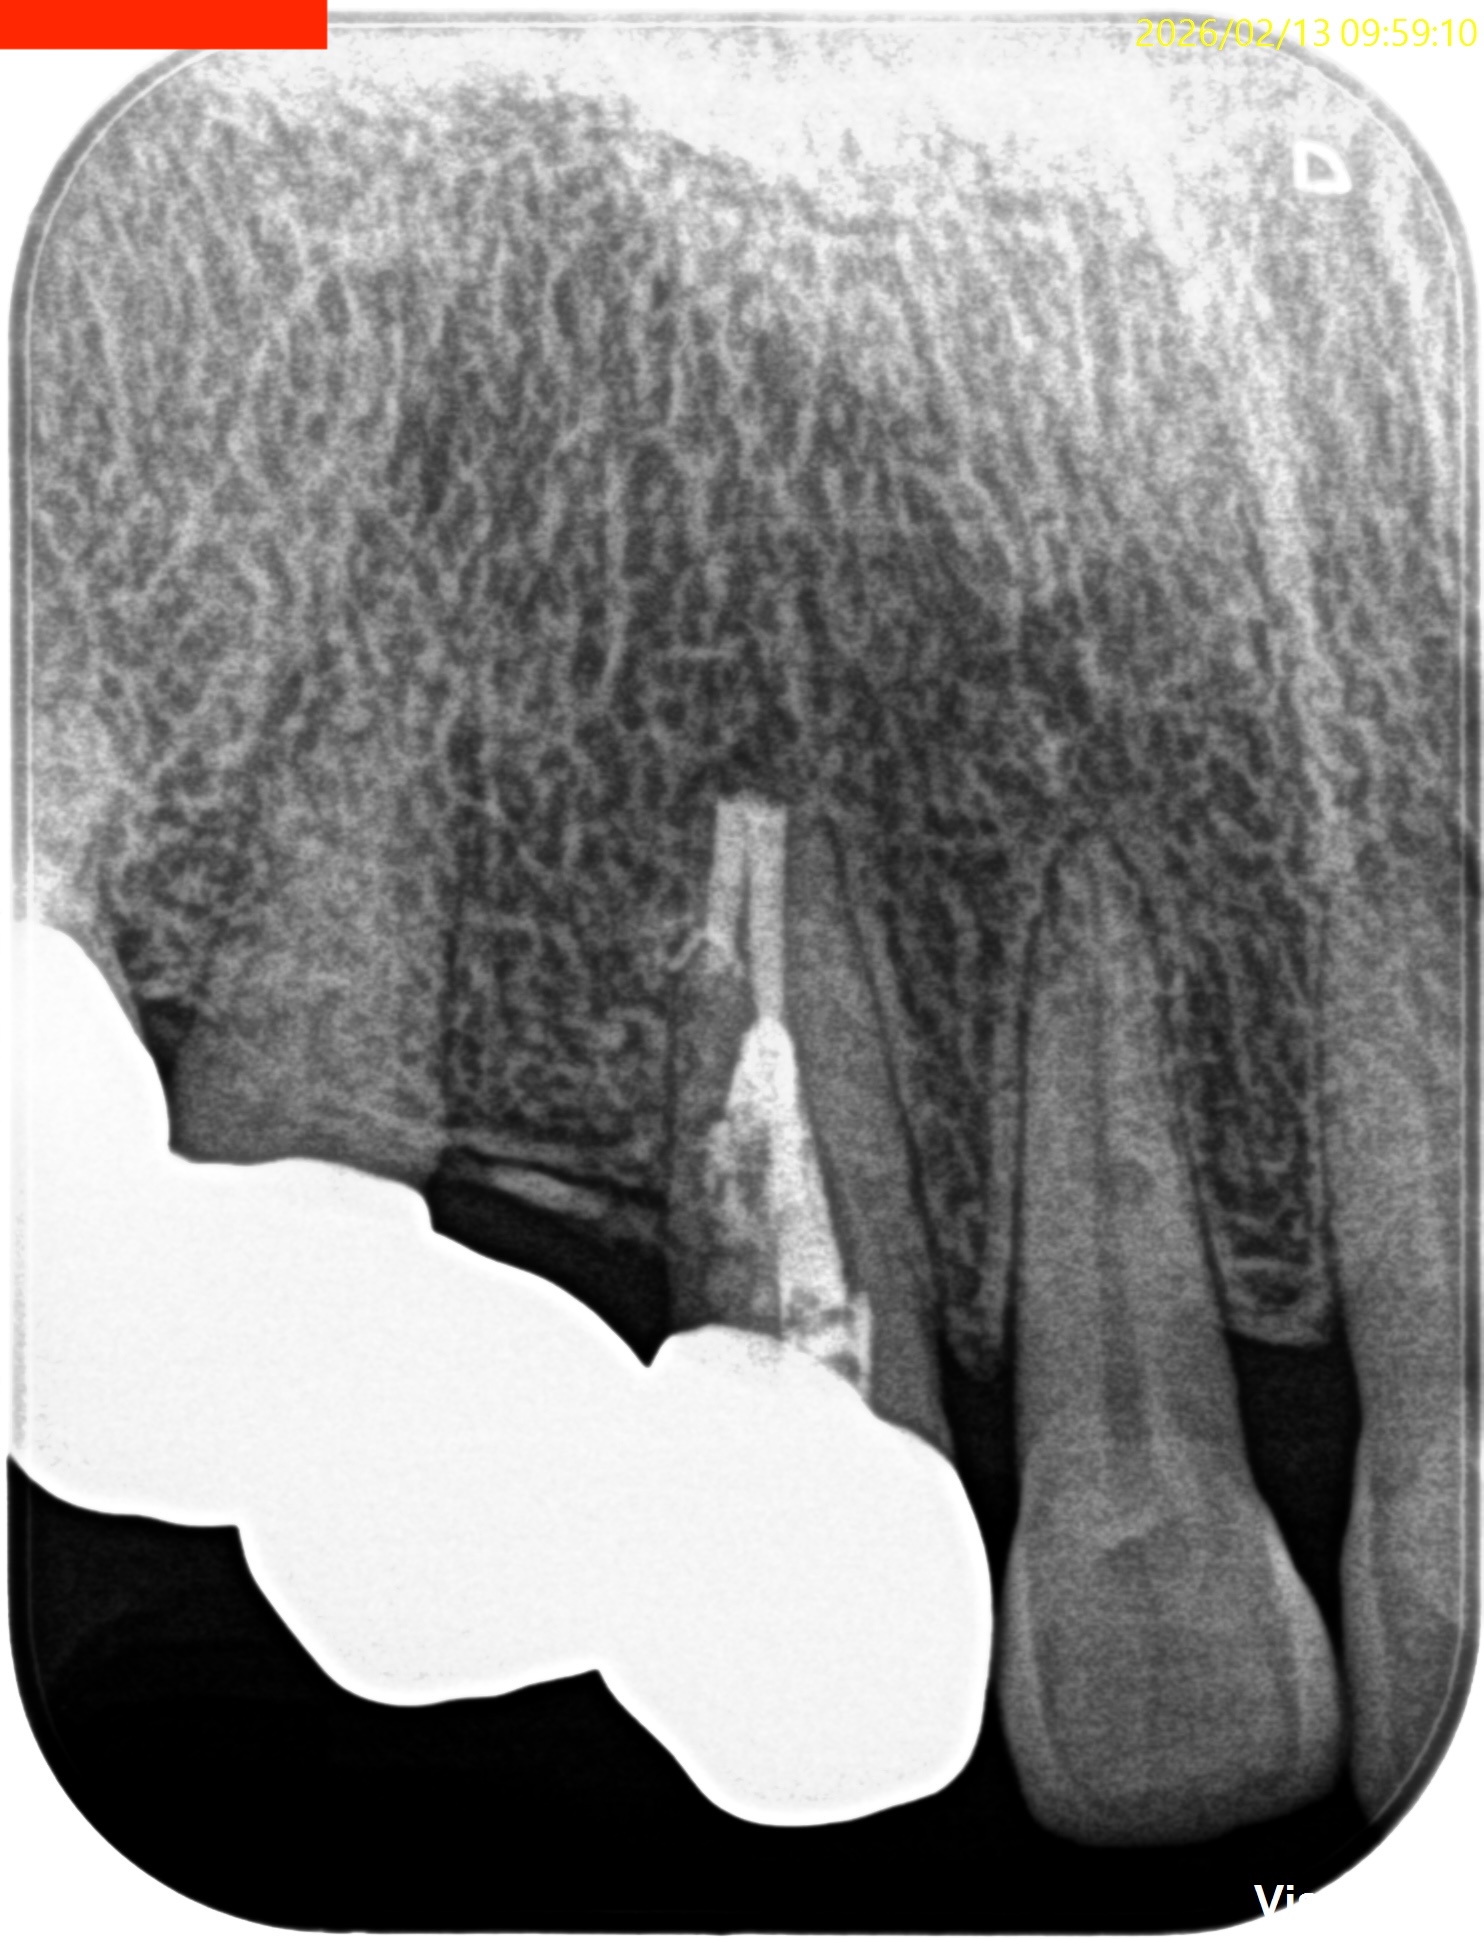

Pre-op Endo test(2025.8.8)

歯牙の表面に外部吸収がある。

学術的には歯髄には及ばないと言われているが画像的には到達済みだろう。

RIL(Radiographic Instrumentation Length)は23mm程度であるが、

PA, CBCTを撮影した。

#6 Invasive Cervical Root Resorption Repair, Apicoectomy 4M recall(2026.2.13)

根切した部分にはだいぶ骨が添加されているし、外部吸収も進展していないようだ。